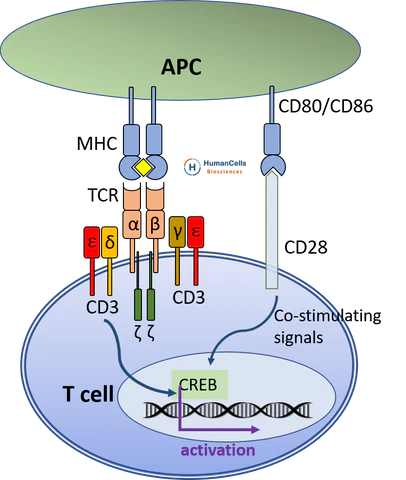

TCR-CD3 complex

- CD3 具有 ITAM ,傳遞活化訊息

- 磷酸化則 ITAM activate

- 6 個分子:ζζ、εδ、γε

T cell 活化

- Adhesion

- Ag-specific activation (primary signal)

- Costimulation

(second signal) - Cytokine signals (third signal)

Primary signal

APC, 確認專一性

- CD4-MHC II → Lck 磷酸化 ITAM

Co-stimulation (second signal)

敵我辨識

T cell 的 CD28 連 B7